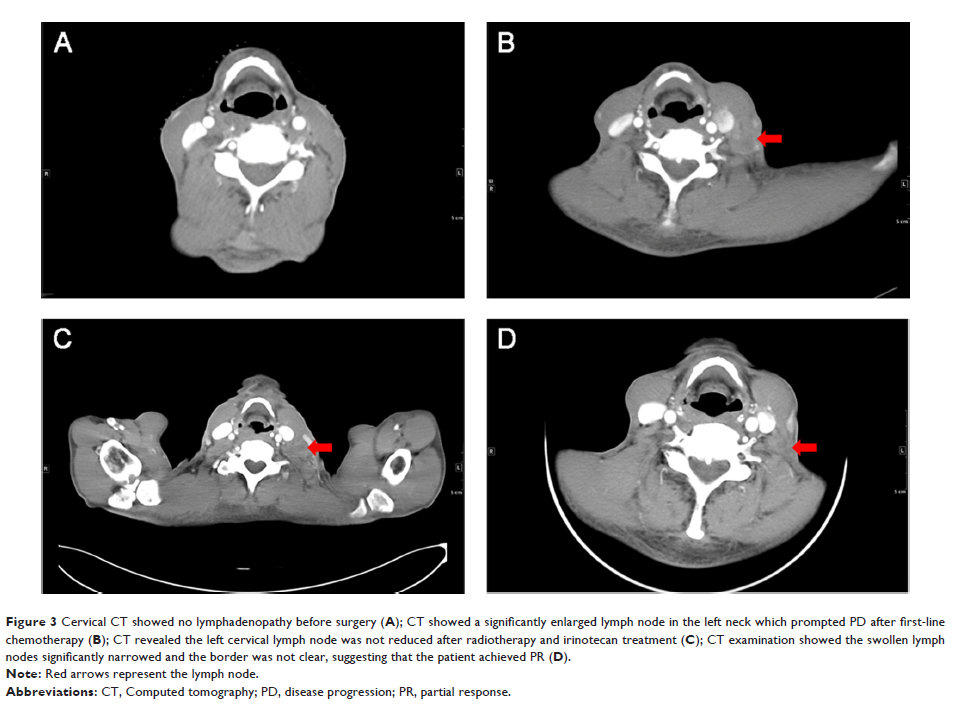

阿帕替尼联合多西他赛治疗转移性食管鳞癌患者一例